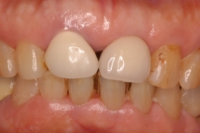

80代女性|前歯の場合

アバットメント装着

補綴物装着

◆治療内容

前歯にインプラントを1本埋入し、アバットメントを装着。

最終的な補綴物を装着しました。